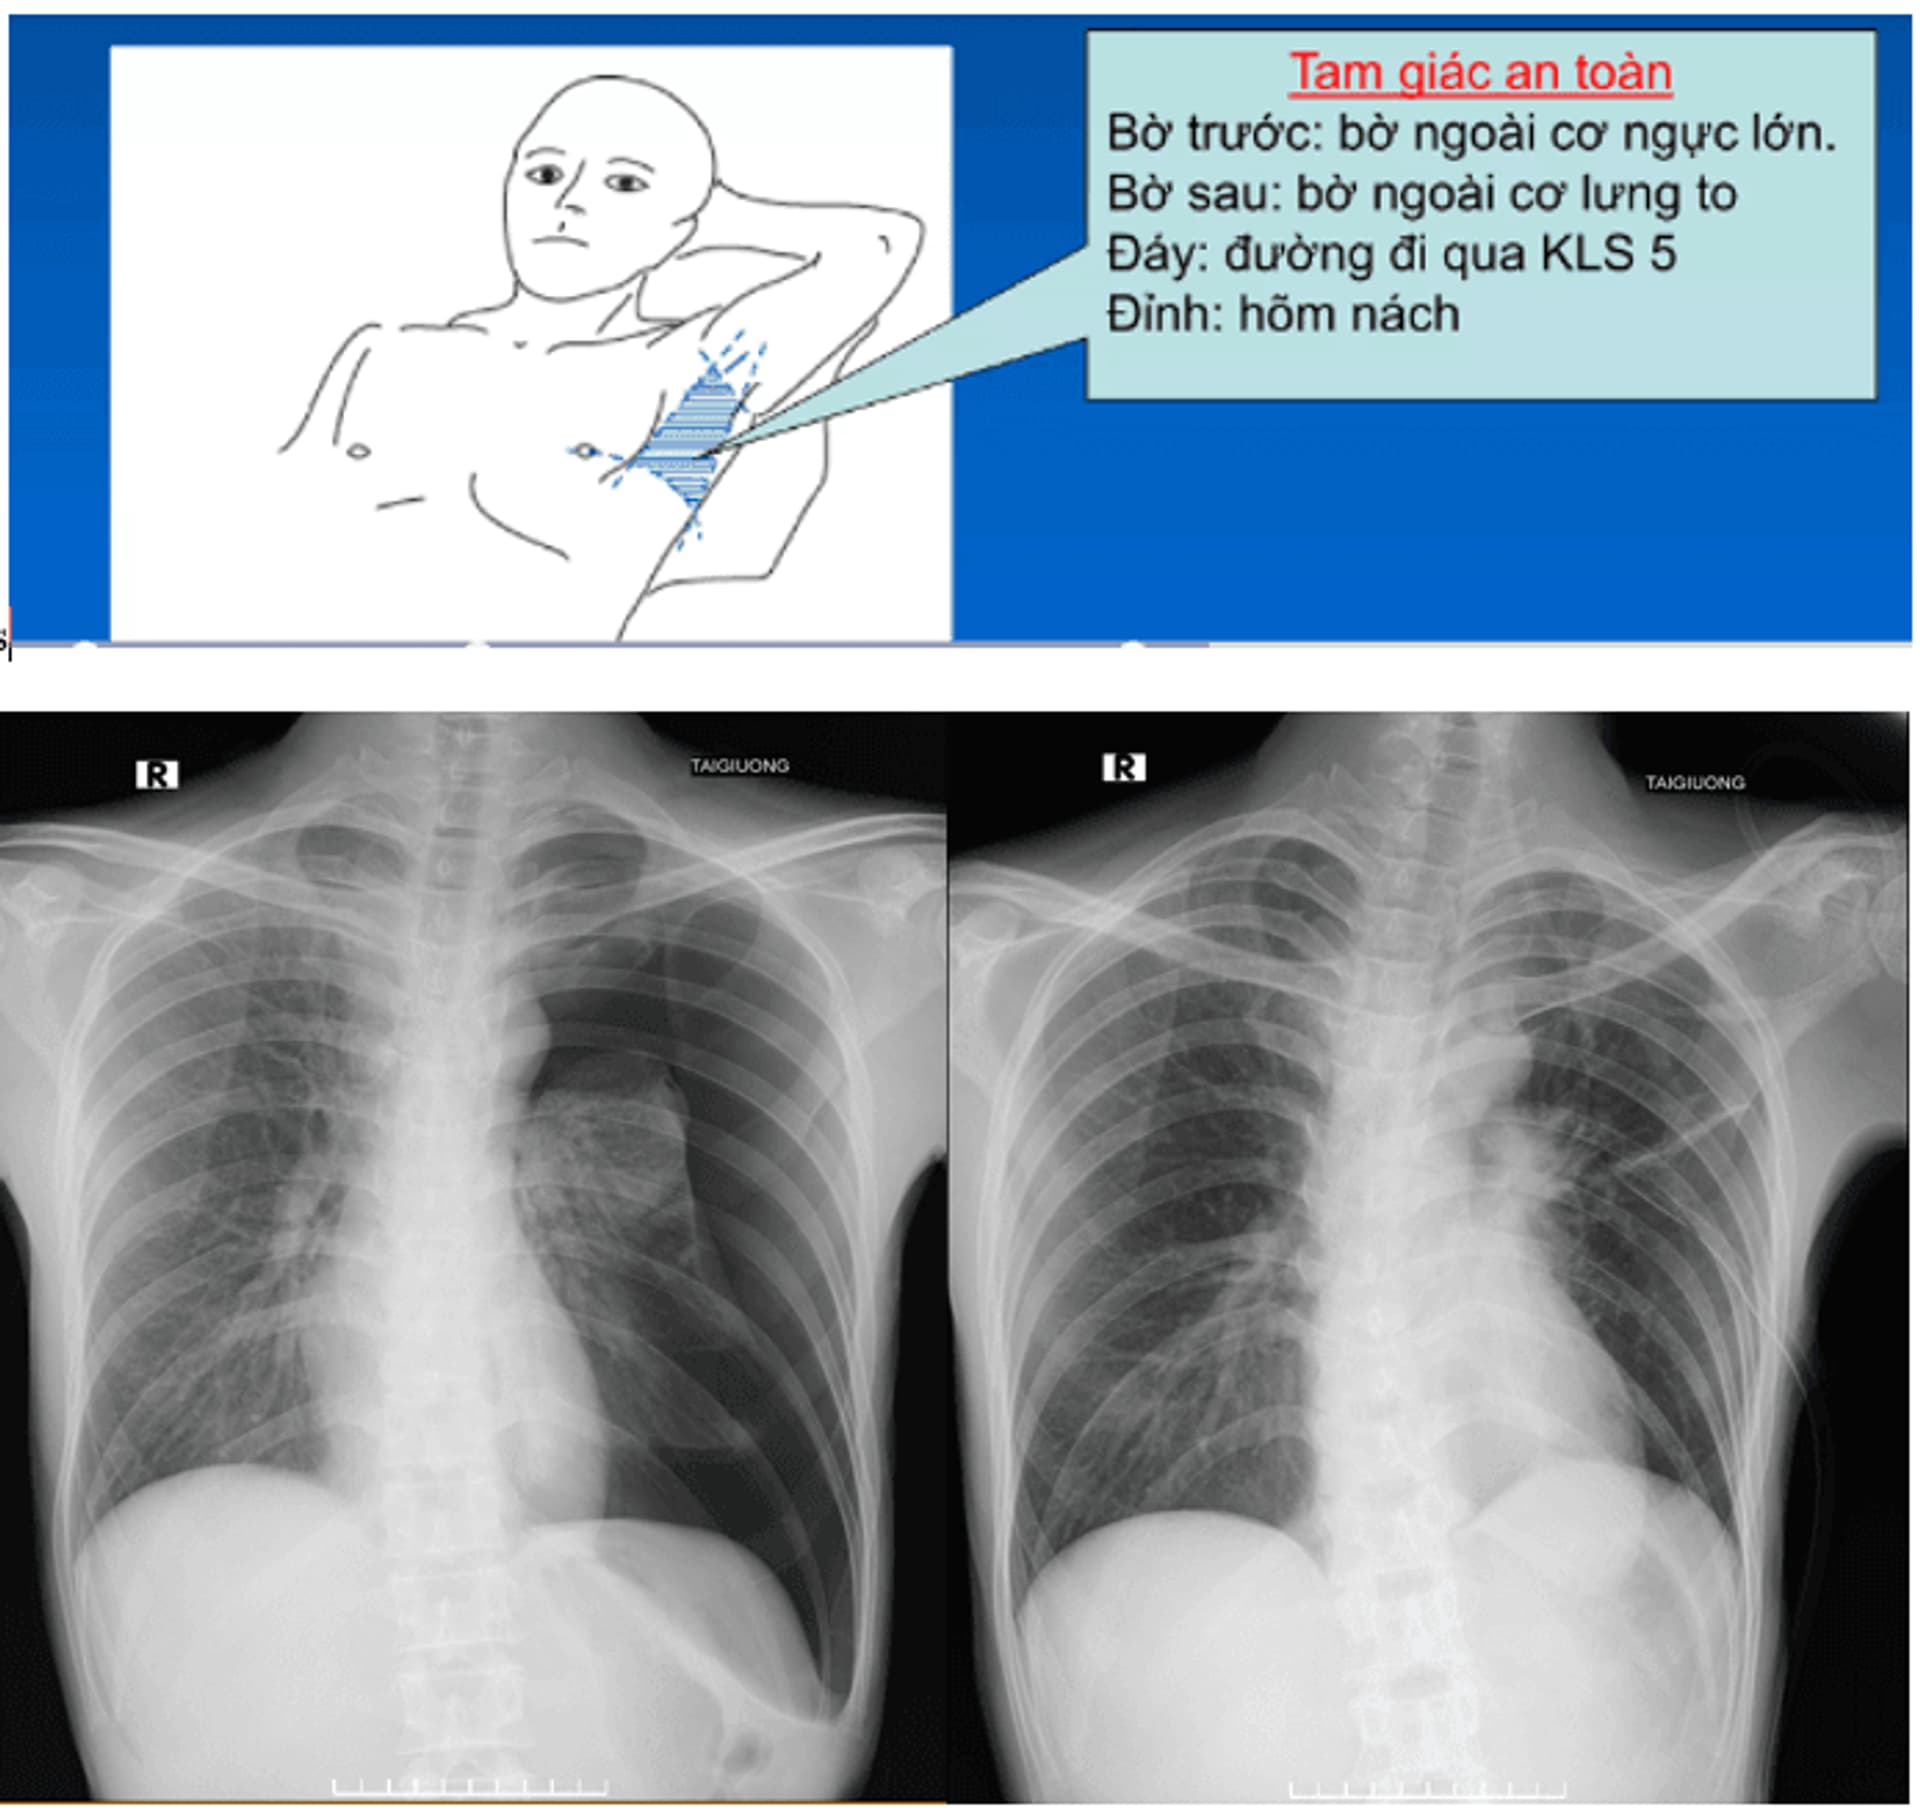

Xác định vị trí dẫn lưu

Dựa trên phim chụp CLVT, hoặc phim chụp XQ ngực để lựa chọn tư thế của người bệnh khi tiến hành thủ thuật.

Hình chụp phim Xquang ngực ở bệnh nhân tràn khí màng phổi trước và sau khi mở màng phổi bằng trocar tại BV Phổi TW